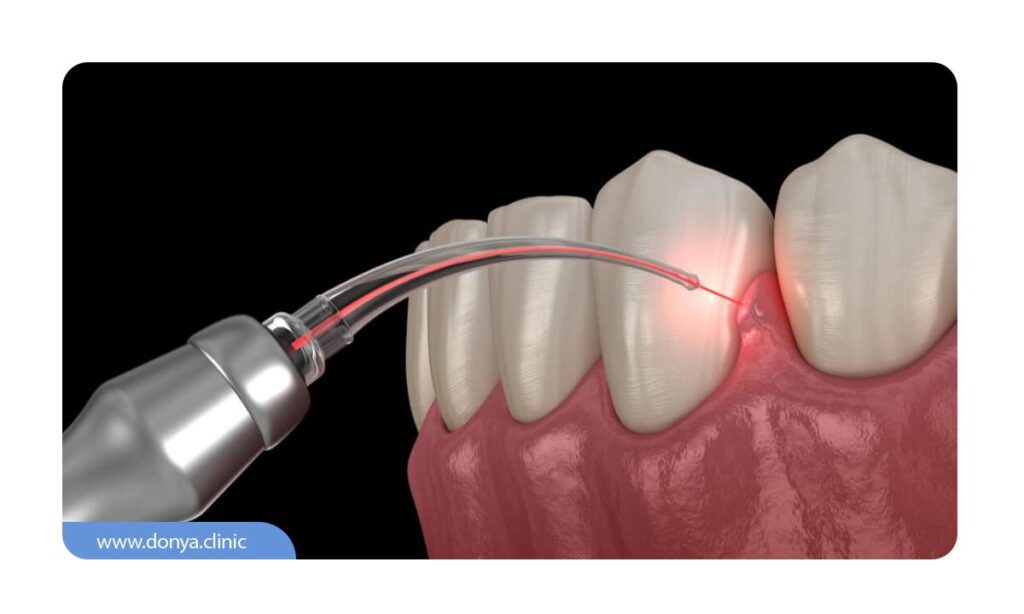

عصب کشی Regenerative Endodontics

این روش، جدیدترین و نوآورانه ترین شکل درمان ریشه است که هدف آن نه فقط حذف عفونت، بلکه بازسازی بافت عصبی داخل دندان است. در Regenerative Endodontics، از تکنیک های زیستی و مواد خاصی استفاده می شود تا سلول های بنیادی تحریک شده و بافت پالپ جدیدی در داخل ریشه رشد کند. این روش بیشتر در نوجوانان یا دندان هایی با ریشه ناقص و باز کاربرد دارد. اگرچه هنوز در مراحل پژوهشی و محدود است، اما نویدبخش درمان هایی است که به جای پر کردن ریشه، آن را زنده نگه می دارند.